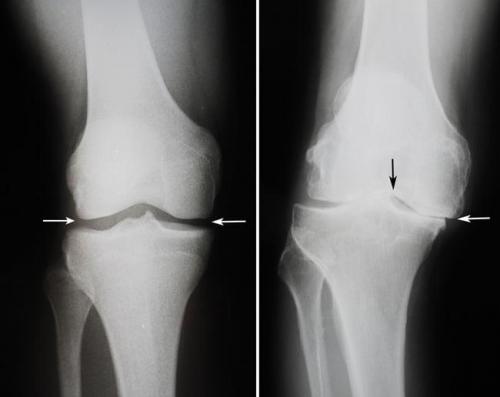

Одно упражнение для колен. Воздействие на колени

При любом поражении колена подходят простые упражнения Сергея Бубновского. Они разработаны для облегчения движений в суставных поверхностях, проверены на миллионах людей. Суть упражнений Сергея Бубновского для коленного сустава проста – активировать местное кровоснабжение для облегчения работы сочленения. Одновременно укрепляется позвоночник, что позволяет уменьшить давление массы тела на пораженные колени. Эффект суставной гимнастики проявляется в следующем:

Повторимся, гимнастика не лечит артроз, это невозможно, но облегчить симптомы она способна.

Однако суставная гимнастика не способна вылечить серьезно измененный сустав . При артрозах, особенно 3-4 степеней , боль сильно не уменьшится, поэтому только операция с целью протезирования окажет радикальный эффект. Однако в восстановительном периоде тренированный организм получит фору при реабилитации, которая пройдет гораздо быстрее.

При таком состоянии кроме операции не поможет ничего.